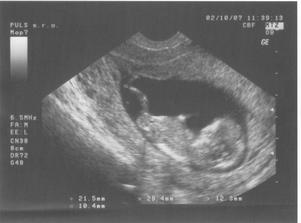

17.8.2007 jsem doma dělala těhu testík a byly 2 //. Poslední kontrola byla 4.9.2007 - 7.tt, velikost miminka 9,6 mm a už bilo srdíčko.Další kontrolu máme 2.10.2007 ... už jsem zvědavá... 2.10.jsem přinesla moč, dostali jsme průkazku a na utz byl vidět pěkný macíček 7,36 cm, čekala jsem o něco málo menší 🙂. Do alba jsem přidala fotečky z utz, ale nejdou popsat - na první - je vidět hlavička, jedna ručička si mne očičko a druhá podpírá hlavičku, okolo tělíčka jsou žebírka, na druhé - je vidět zadeček s nohama křížem ... to je pohodička a na třetí - je celé miminko s nožkama nahoře ..pěkně odpočívá. Jinak bylo vše vpořádku, další kontrola bude 1.11.2007-kontrola, mimís měřil přes 14,5 cm a vážil 189 g. Při kontrole pásl koníčky 🙂. Konečně mi vzali krev asi už na vícero vyšetření najednou. Další návštěvu máme 27.11. ... kontrola byla velmi rychlá, miminek zase pekně pózoval a rozesmíval pana doktora i mě. Chvíli se dívalo nahoru, pak se kokulo na nás z očí do očí. Všechny testy dopadly dobře - triple test i rozbor krve, tak si jen přeju, aby to tak bylo i nadále. Příští kontrolu 3.1.2008 už nebude vidět miminko na ultrazvuku celé, protože už bude moc velké, tak to už se budu dívat jen na jednotlivé části tělíčka 🙂.3.1.2008 byla kontrola ještě rychlejší 🙂, pan doktor zkontroloval srdíčko, jestli ťuká. Při odchodu jsem dostala žádanku na odběry k těhotenské cukrovce, bylo to jen male píchnutí do prstu, s vypitím glukósy v černém čaji. Příští kontrola je 29.1.2008, jsem zvědavá jak dlouho budu ještě moct chodit do práce.Miminko už se má pěkně k světu, už i tatínka kope přes bříško 🙂). Další kontroly probíhaly většinou vpořádku, akorát během února se panu doktorovi zdálo mimi malé, tak jsme čekali jestli doroste, a povedlo se. Doktor t ozdůvodnil tak, že miminka nemusí růst podle průměru, ale podle toho jak se jim chce, což je samozřejmě logické. Nechtěla jsem vedět pohlaví, spíš se těším na překvapení u porodu. Do práce jsem chodila, co to nejdýl šlo, všechno bylo vpořádku. Jen mi při posledním odběru zjistili pozitivní protilátky, tak mi je hlídají a na endokrinologii mi předepsali užívání jodu. Na další kontrolu půjdeme 4.4. do porodnice v Podolí. Kontrol v Podolí bylo ještě několik. V den termínu porodu jsem šla na delší procházku, večer upekla buchty a navařila a ono nic. Poslíčci mě strašili celkem dva týdny, ale vždycky to přešlo. Nakonec jsme museli jít na vyvolání 2.5.2008.